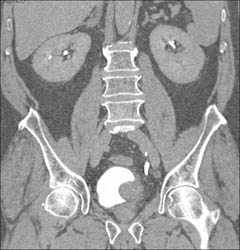

Bladder Cancer